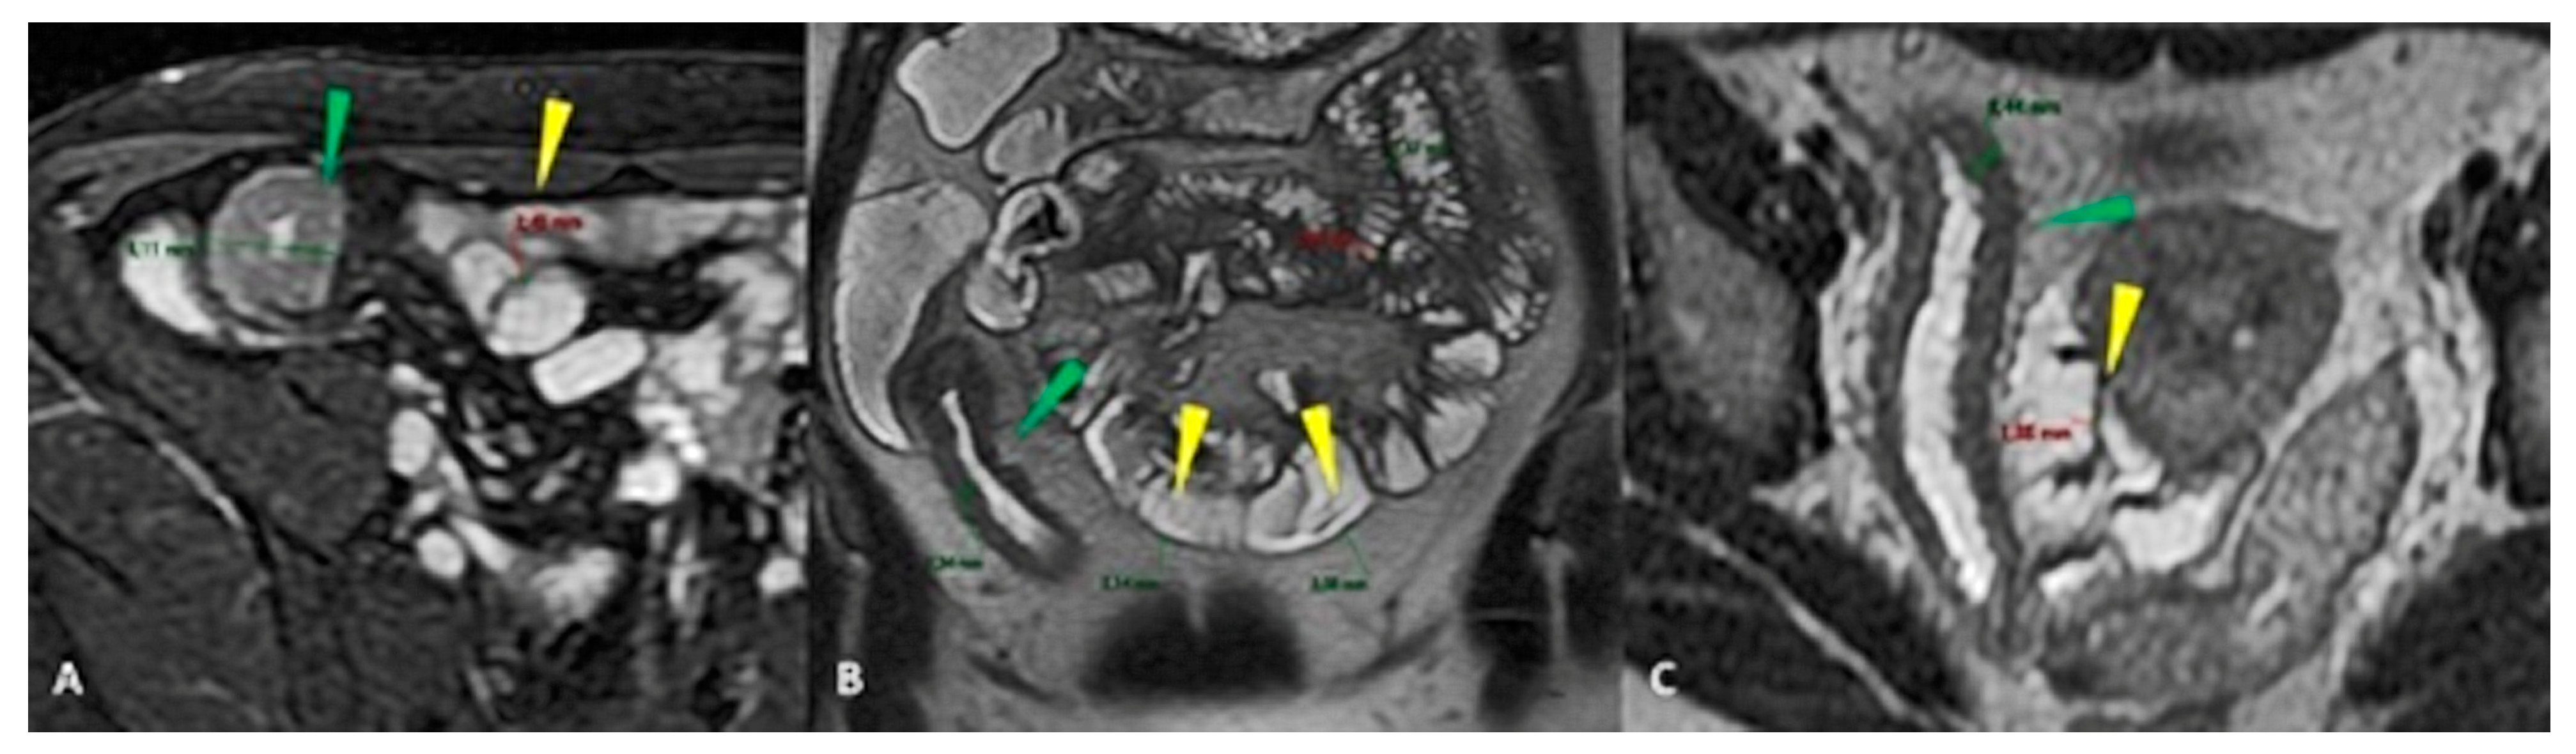

- Cronin, C.G.; Delappe, E.; Lohan, D.G.; Roche, C.; Murphy, J.M. Normal small bowel wall characteristics on MR enterography. Eur. J. Radiol. 2010, 75, 207–211. [Google Scholar] [CrossRef]

| Jejunum | Proximal Ileum | Distal Ileum | Terminal Ileum |

|---|---|---|---|

| 24.5 mm (S.D. = 4.2 mm) | 19.5 mm (S.D. = 3.6 mm) | 18.9 mm (S.D. = 4.2 mm) | 18.7 mm (S.D. = 3.6 mm) |